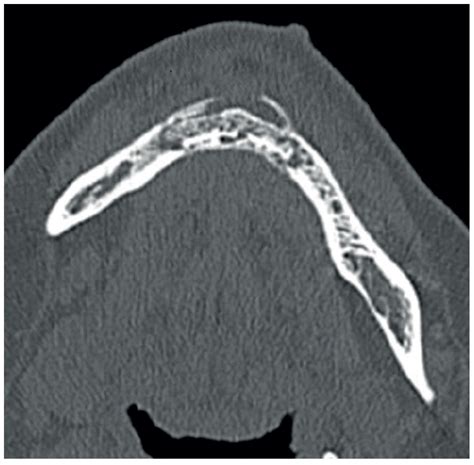

Medication-Related Osteonecrosis of the Mandible Treated with Marginal ...

mdpi.com